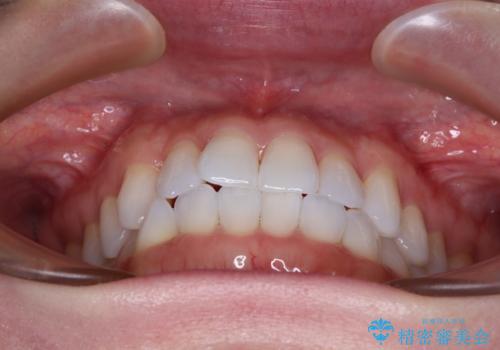

前歯のデコボコをインビザラインで綺麗に

- 11ヶ月

- 5-10回

- 上下前歯の叢生を気にして来院された患者様です。

インビザラインでの治療を希望されていて、デコボコの程度が中等度であり、安価なパッケージにて対応可能と判断されたため、インビザライン・モデレートを用いて矯正治療を行うこととしました。